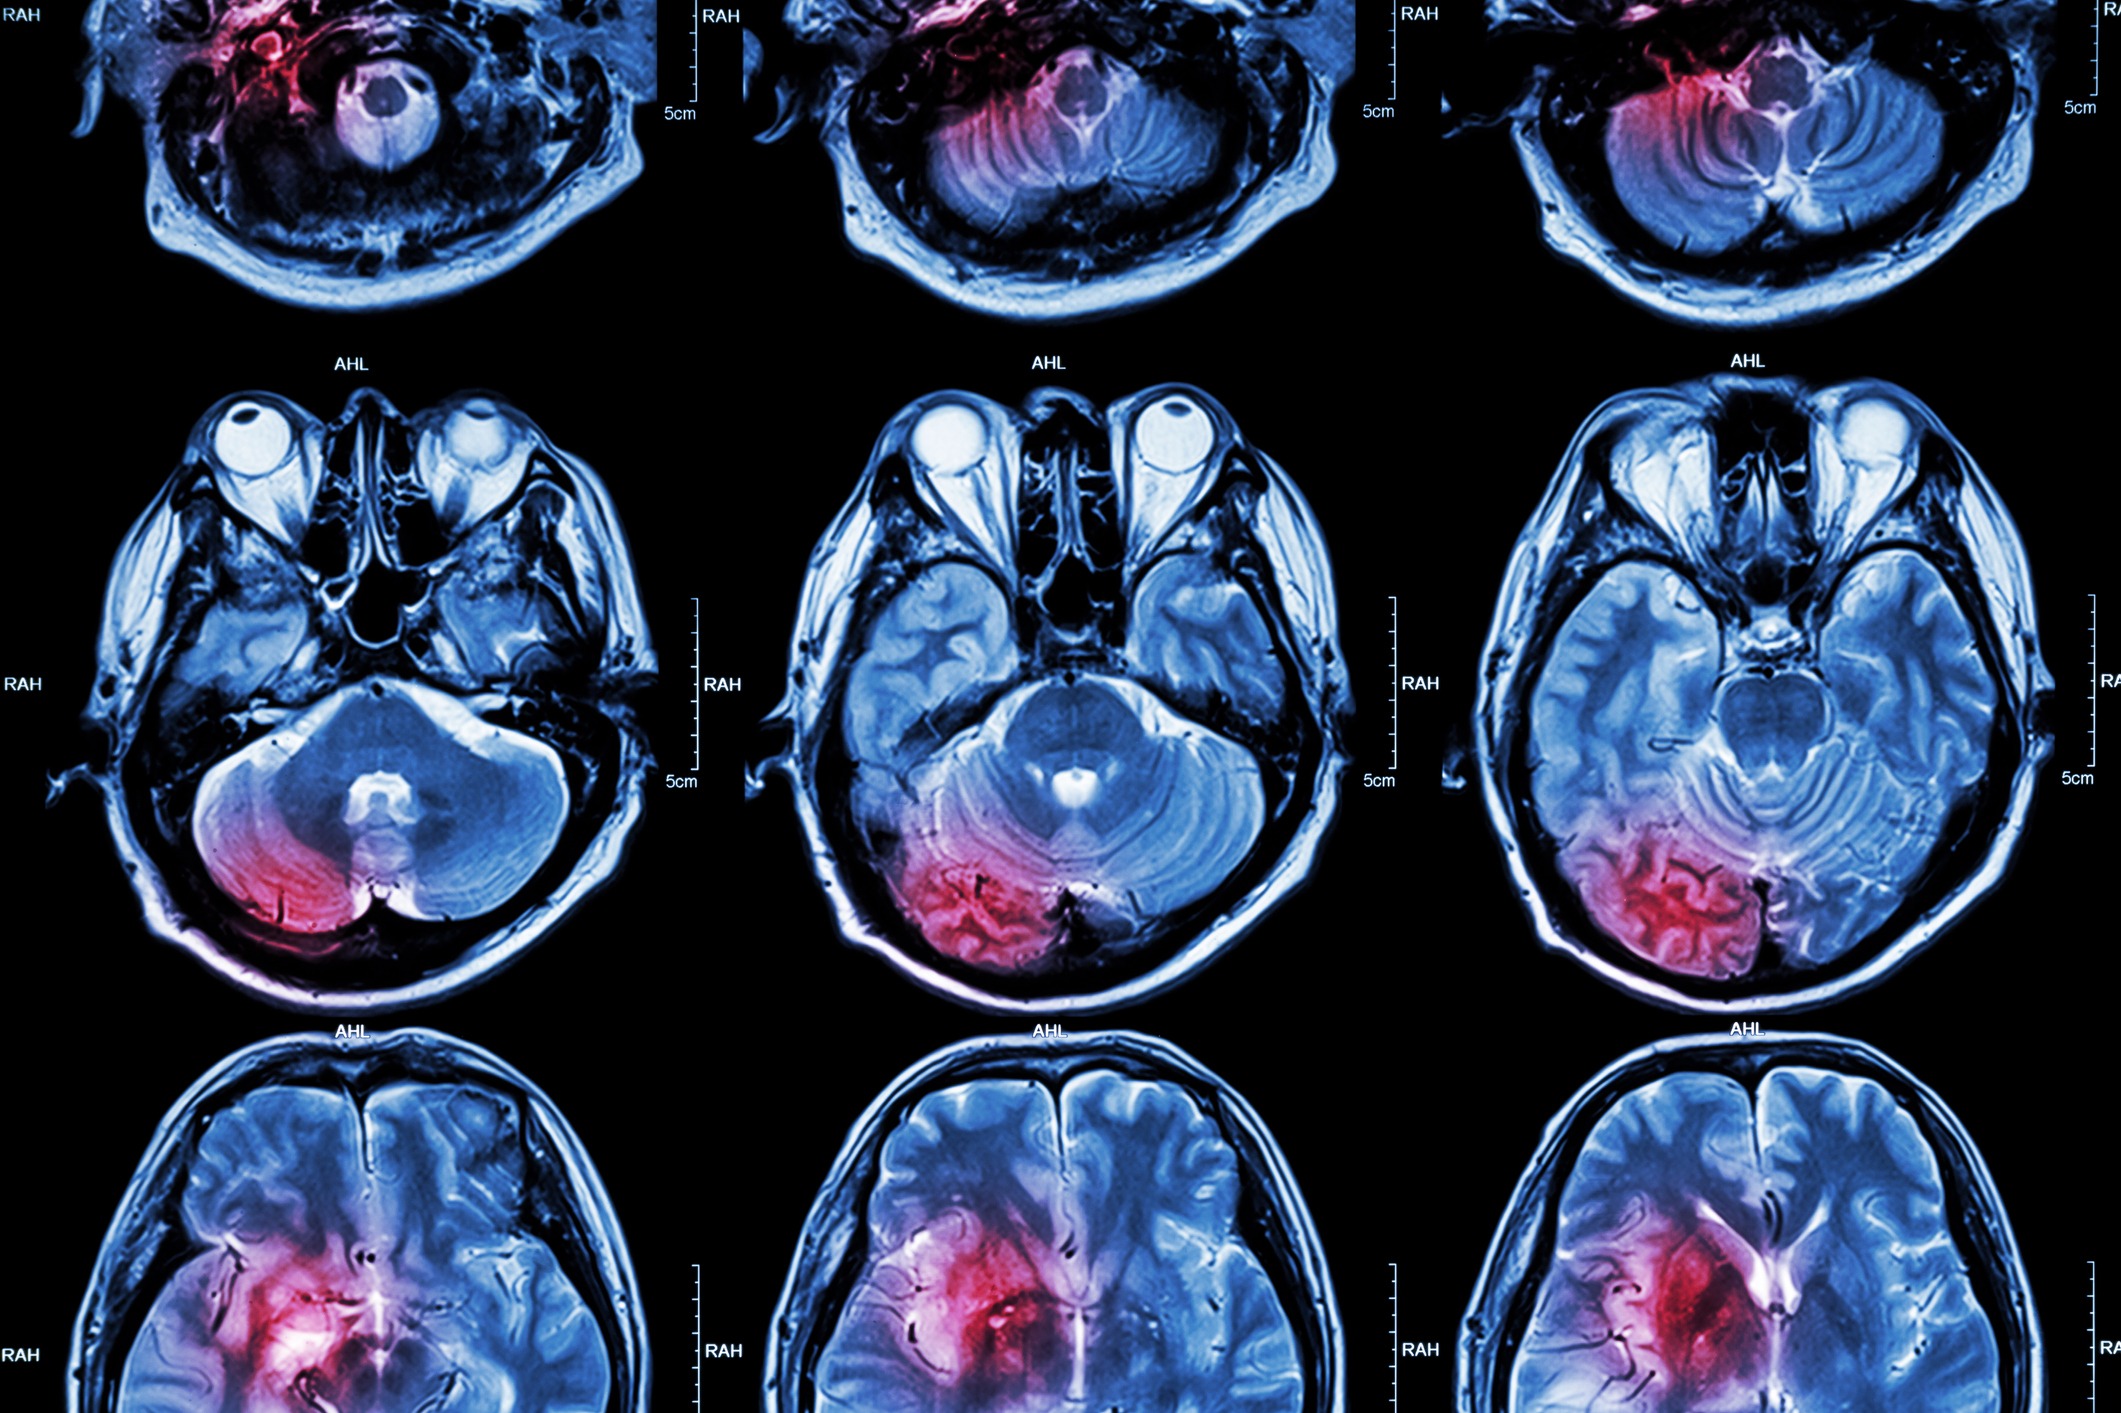

Dans le domaine de la neurologie, le scanner cérébral est fréquemment utilisé pour diagnostiquer ou surveiller l’évolution de troubles neurologiques, tels que des accidents vasculaires cérébraux (AVC) ischémiques ou hémorragiques.

Dans de nombreux cas, pour une évaluation plus détaillée de la tumeur, d’autres modalités d’imagerie telles que l’IRM (imagerie par résonance magnétique) peuvent être recommandées. L’IRM offre des informations supplémentaires sur la composition tissulaire de la tumeur et ses interactions avec les structures environnantes, fournissant ainsi une vision plus complète pour le diagnostic et la planification du traitement.

En revanche, l’IRM cérébrale repose sur des champs magnétiques et des ondes radio, éliminant l’exposition aux rayons X. Elle excelle dans la visualisation des tissus mous, des nerfs et des vaisseaux sanguins, ce qui en fait un choix privilégié pour évaluer les troubles neurologiques, les tumeurs cérébrales et d’autres affections sans les préoccupations liées aux radiations.